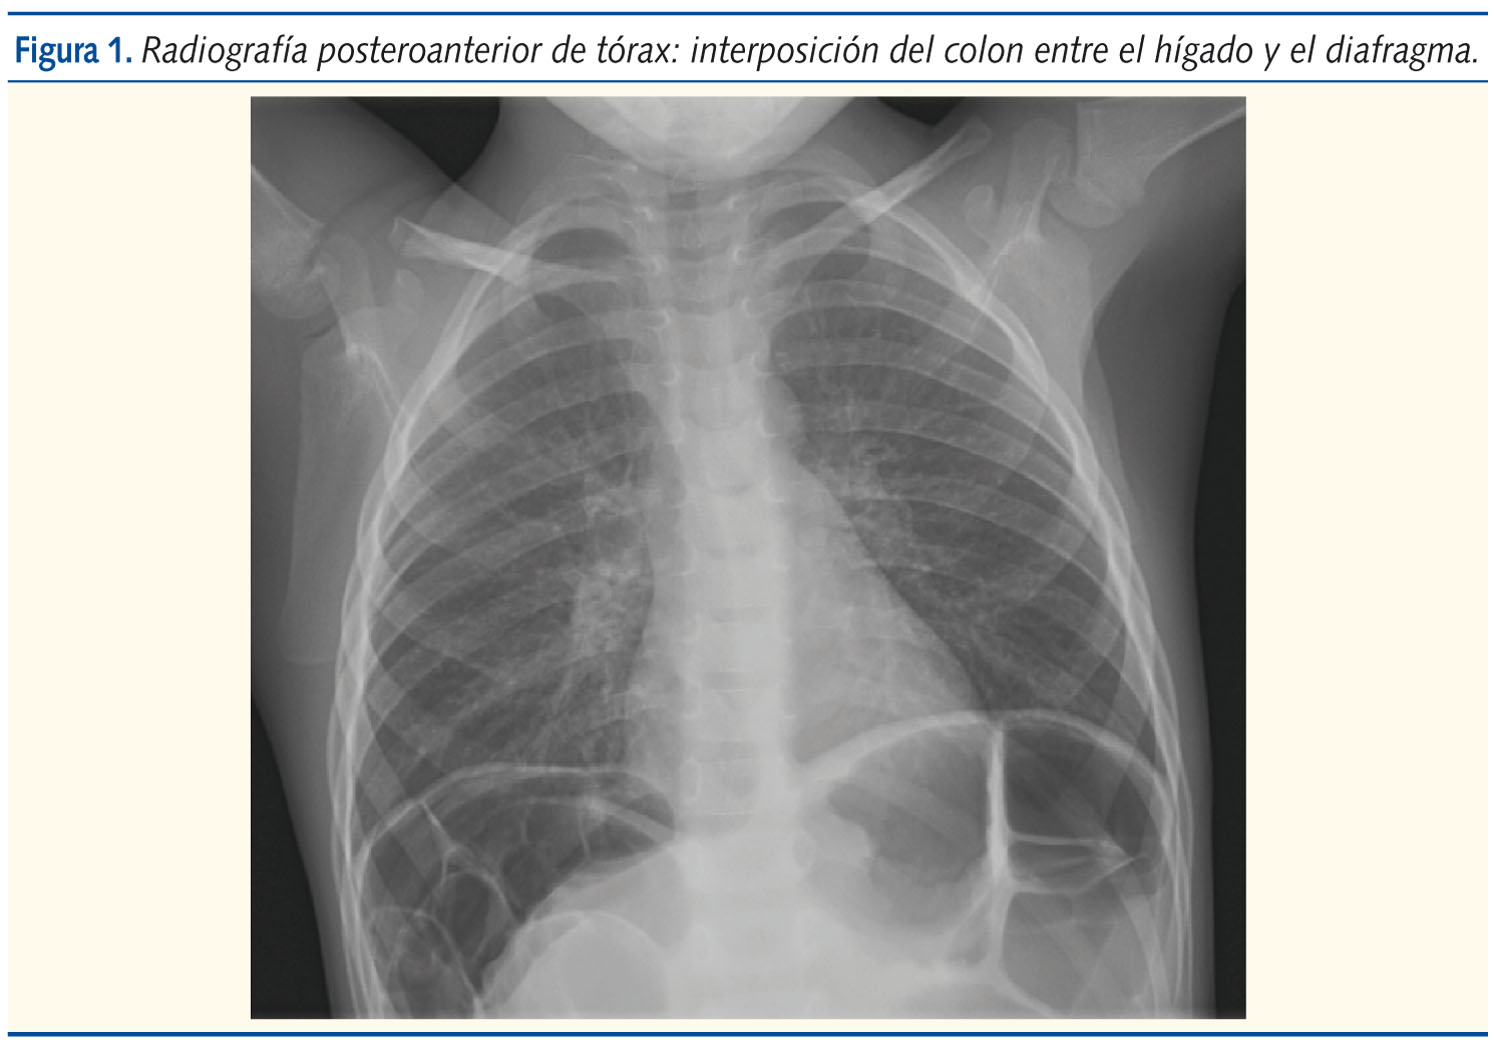

Dada la exploración del paciente, se solicita radiografía de abdomen, en la cual se evidencia interposición del colon entre el hígado y el diafragma (figura 1).

En la exploración es frecuente encontrar distensión abdominal y descenso del hígado por el colon. La radiografía toracoabdominal puede ser suficiente pero no diagnóstica; en ella, aparecerá una masa de densidad aire entre el hemidiafragama derecho y el hígado. Así, se puede realizar el diagnóstico diferencial con neumoperitoneo, abceso subfrénico, neumatosis intestinal, quiste hidatídico infectado y tumores hepáticos1.